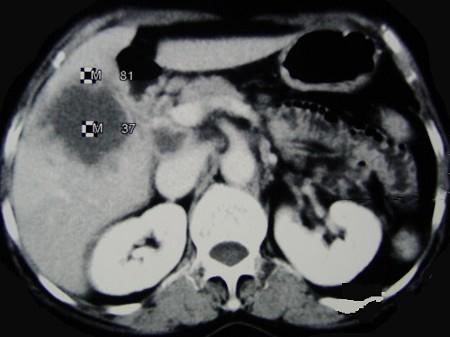

问题 女,65岁,右季肋区疼痛二个月,CT扫描所见如图,最可能的诊断是()

选项 A.慢性胆囊炎 B.胆囊癌腹膜后淋巴结转移 C.胆管细胞癌 D.胆囊黄色肉芽肿 E.胆囊腺肌增生症

答案 B